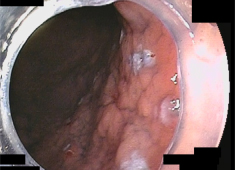

近年、新しい内視鏡の機器が開発され、内視鏡的粘膜下層剥離術(ESD)という新しい内視鏡治療が可能になりました。ESDはITナイフという特殊な電気メスを用いて粘膜下層を剥離できるためEMRでは対応できなかった2cm以上の広い範囲の早期胃がんにも対応でき、より大きな病変の一括した切除ができるようになりました。

内視鏡的に行うため胃を切除することなく病変を切除することができます。